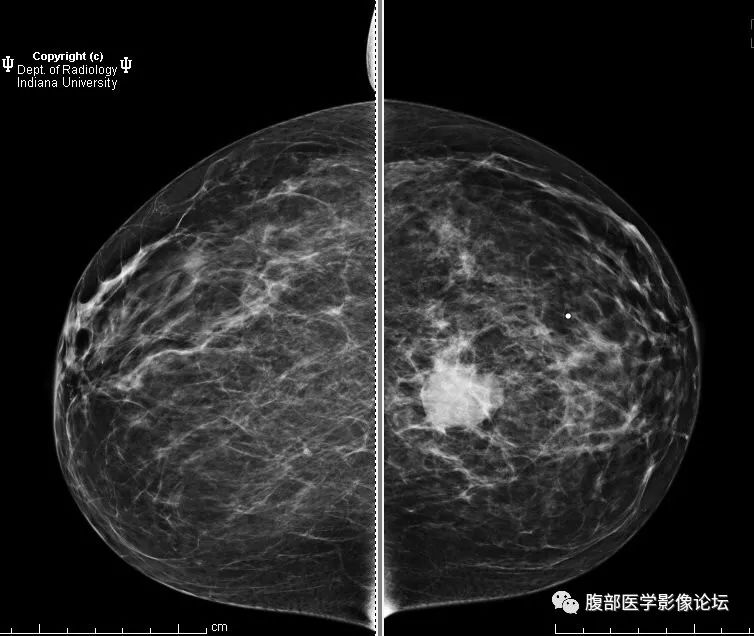

ductalcarcinoma

医学影像英语每日读丨95invasiveductalcarcinoma